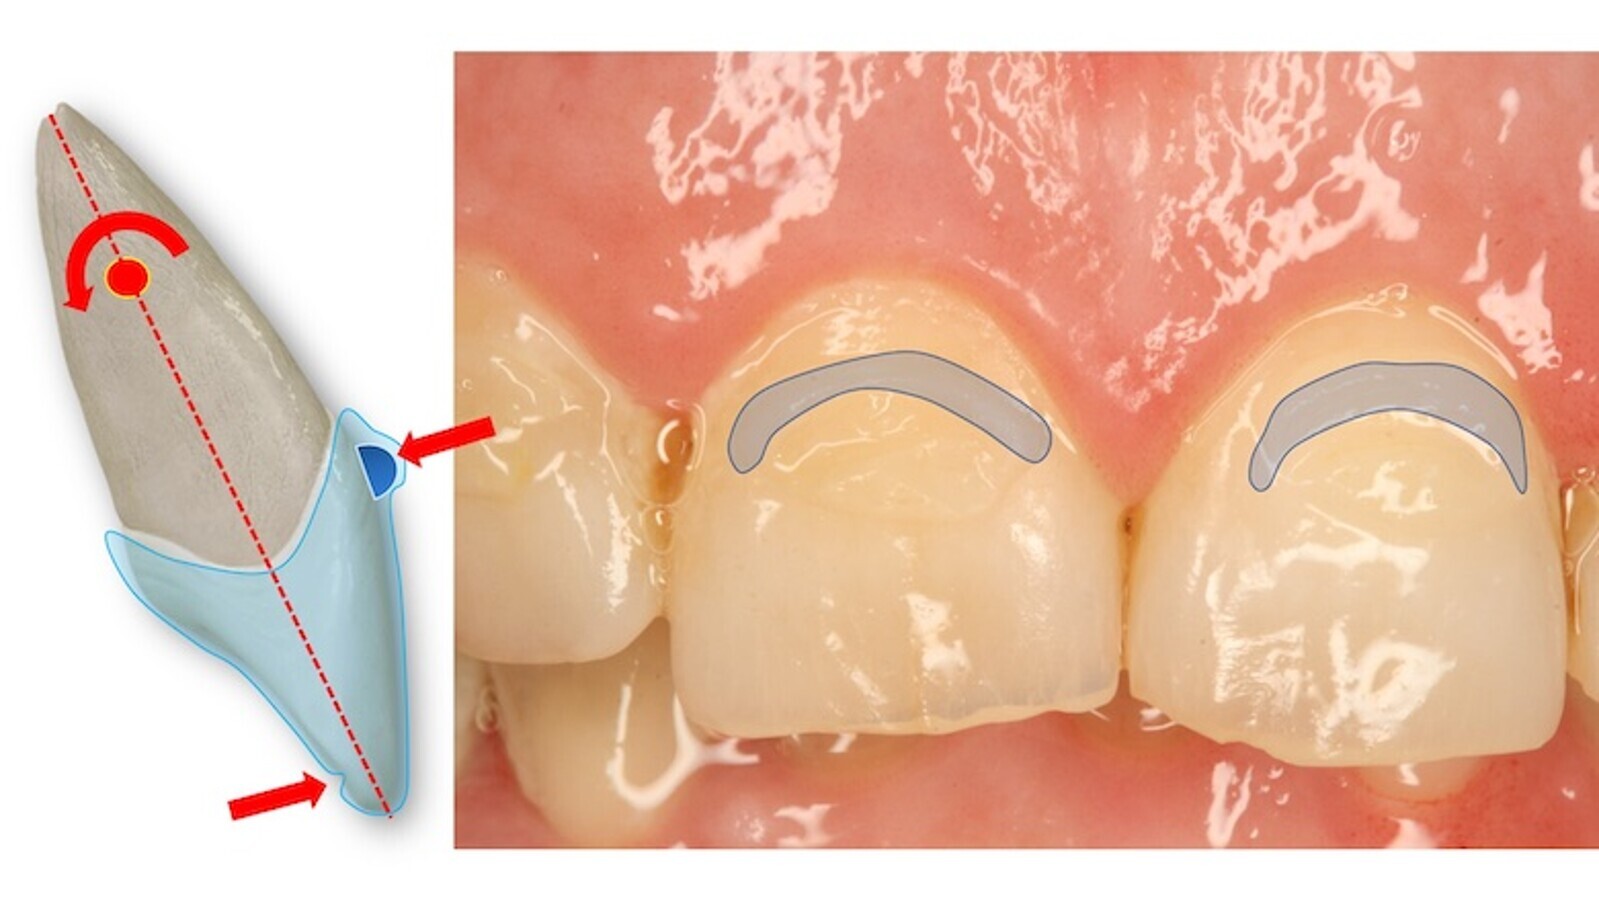

Elevación o Arco de Torque: Se sitúan próximos al borde gingival de los incisivos y buscan crear un par de fuerzas coordinadas con un punto de presión inciso-palatino (figuras 34 y 35).

Figuras 34-35. Se sitúan próximos al borde gingival de los incisivos y buscan crear un par de fuerzas coordinadas con un punto de presión inciso-palatino.

La distancia entre estos dos puntos crea un momento que combina la vestibulización de la corona (limitada por el alineador) con una fuerza palatina sobre esta elevación o arco de torque que desplaza el centro de giro o rotación hacia incisal. Haciendo un paralelismo con la biomecánica clásica con brackets, el par de fuerzas que aparece por la deflexión del alambre en la ranura (alrededor de su eje mayor) vendrían a ser ahora las dos fuerzas (una sobre el punto de presión inciso-palatino y la otra, de igual magnitud y sentido contrario, la ejercida sobre la mencionada elevación o arco de torque), mientras que la fuerza distal del arco (que anula en parte uno de los vectores del par de fuerzas) aquí viene representada por el propio alineador abrazando toda la corona dentaria.

Es importante analizar el eje mayor del diente y la colocación del atache respecto al mismo, así como los pares de fuerzas que se generan en las distintas facetas activas (figura 58).

Figura 58. Análisis del eje mayor del diente y de la colocación del atache respecto al mismo, así como de los pares de fuerzas que se generan en las distintas facetas activas.